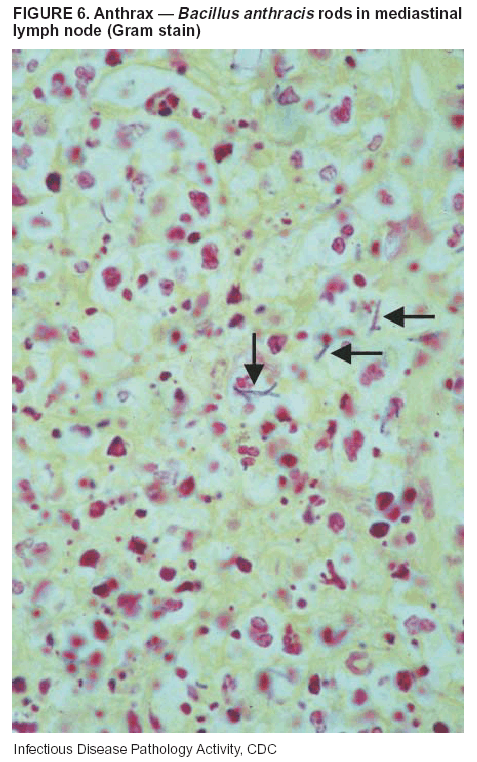

Diagnostic Tests. If the patient has not received antibiotics, bacilli can be observed in tissues with H&E, Gram, and silver impregnation stains and IHC assays (Figures 6 and 7). However, after antibiotic treatment has been instituted, only silver stains and IHC assays will highlight the bacilli. IHC assays for B. anthracis can demonstrate bacilli, bacillary fragments, and granular bacterial fragments in formalin-fixed tissues, even after 10 days of antibiotic treatment. Although a DFA test is available for B. anthracis, it is not used on formalin-fixed tissues.